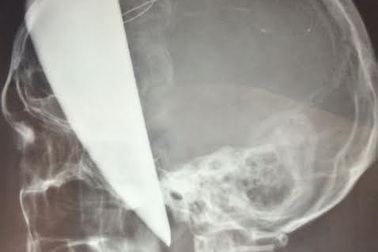

Cứu bệnh nhân bị dao bầu đâm xuyên nãoBệnh nhân N.V.V (25 tuổi, Thanh Hóa) được chuyển đến bệnh viện (BV) Việt Đức trong tình trạng con dao bầu dài 40cm cắm trên vùng đầu, xuyên vào não nguy kịch.